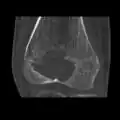

1. a. X-ray of chondroblastoma of thigh bone near knee

1. b. CT scan shows chondroblastoma of thigh bone near knee more clearly

1. c. CT scan of chondroblastoma of thigh bone near knee (cross-section view)